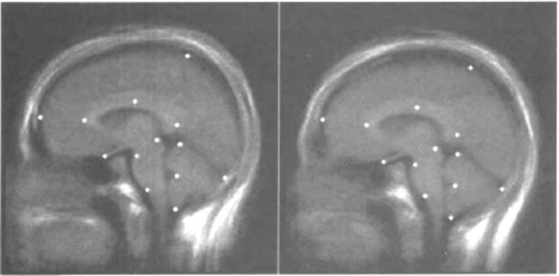

Anatomically corresponding points (landmarks) are chosen on the two objects, say the ordered set of points on the first object, and the ordered set of points on the second object. They are translated to place their centroids at the origin, and then the Procrustes procedure is applied by seeking a rigid motion of 3-space so as to minimize the disparity between and , where .

In Figure 18, the left brain slice is actually an average over a group of doctors, and the right slice an average over a group of patients, each with 13 corresponding landmark points, from the paper by Bookstein [1997].

If size is not important in the comparison of two shapes, then it can be factored out by scaling the two sets of landmarks, and , so that .

For modifications which allow comparison of any number of shapes at the same time, see for example Rohlf and Slice [1990].